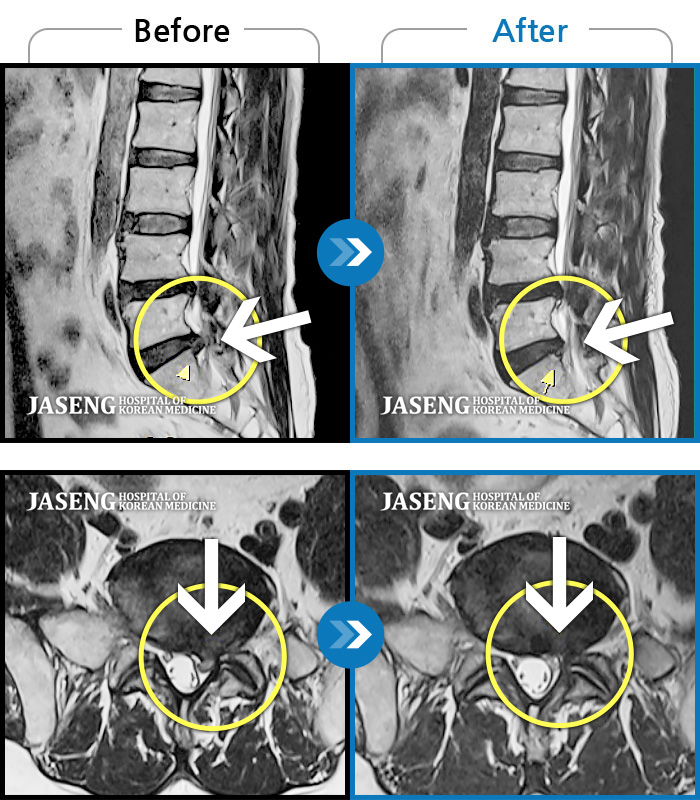

허리디스크

도움받은 사례

광주 · 장영우 원장

양측 허리부터 좌측 다리까지 이어지는 저림과 통증으로 걷기 힘들어 내원하였습니다.

촬영시기

2024.11.22 ~ 2025.05.16

2025.05.30

조회수 284